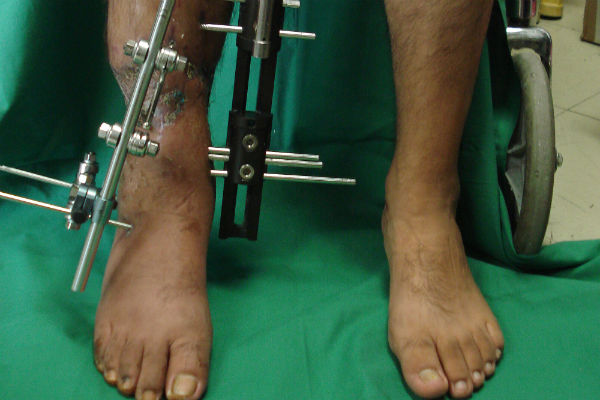

La doctora Fryda Medina Rodríguez, Directora General de la UMAE y quien encabeza el equipo de cirugía, explicó que esta técnica consiste en varios procedimientos: primero se retira el tejido muscular muerto, después se coloca una barra y un tornillo -que permanecen fijos a la extremidad-, y se realiza una incisión en la parte superior del hueso.

Posteriormente se coloca una esponja que ayuda a la regeneración de los tejidos. El aditamento empuja la masa muscular sin obstruir los vasos sanguíneos, y se cubre con piel el tejido expuesto.

Explicó que la elongación ósea permite que el hueso se alargue un milímetro por día, al hacer girar el tornillo 45 grados cada seis horas, día y noche; acción que el paciente debe realizar una vez que es dado de alta del hospital.

De esta manera se logra que la masa ósea, músculo, piel y tejidos se regeneren hasta alcanzar los centímetros de longitud perdidos en menos de un año.